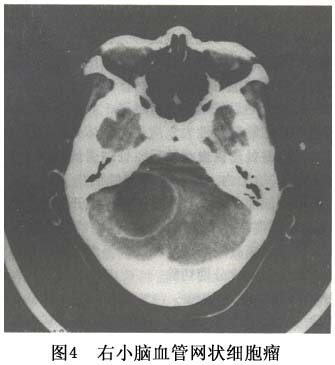

3.CT 典型表现为大囊内有小的瘤结节影,瘤结节和实性肿瘤呈等密度并均一强化,囊壁不强化。实质性肿瘤CT显示为类圆形高密度影像,密度不均匀;囊性者显示为低密度,较其他囊肿密度高,边缘欠清晰,可见高密度结节突向囊腔内。增强后囊壁密度多无变化,瘤结节呈均匀增强。肿瘤周围可见低密度水肿带。有人根据CT表现将之分为囊肿结节型、囊肿型、实体型及脑积水四型(图1,2)。

4.MRI 肿瘤T1像信号高于脑脊液为等T1;T2像为长T2信号,并可见肿瘤周围水肿带或小的血管流空影见图3,图4。此病应注意与小儿常见的后颅凹囊性星形细胞瘤鉴别。 医学百科网 | YxBaike.Com